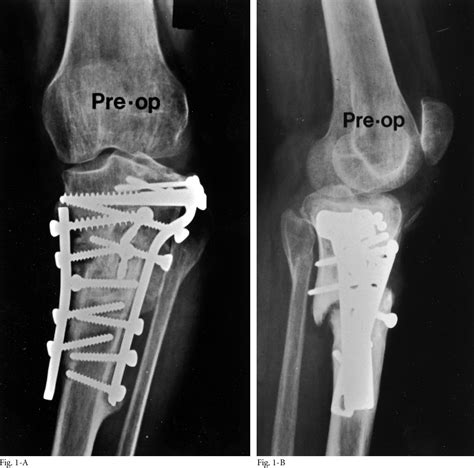

The journey through Open Reduction Internal Fixation Surgery begins with pre-operative preparation, including imaging like X-rays or CT scans. During the procedure, the surgeon follows a systematic approach to ensure safety and precision.

4. Fixation Plates, screws, or intramedullary rods are attached to stabilize the bone.

• Follow-up Imaging: Periodic X-rays are taken to monitor bone union and ensure the hardware remains properly positioned.

Hardware, such as metal plates or screws, is often left inside the body indefinitely. In most cases, these materials are biocompatible and do not cause issues. However, if the hardware becomes uncomfortable or causes localized irritation, surgeons may discuss a secondary, minor surgery to remove it after the bone has fully remodeled.